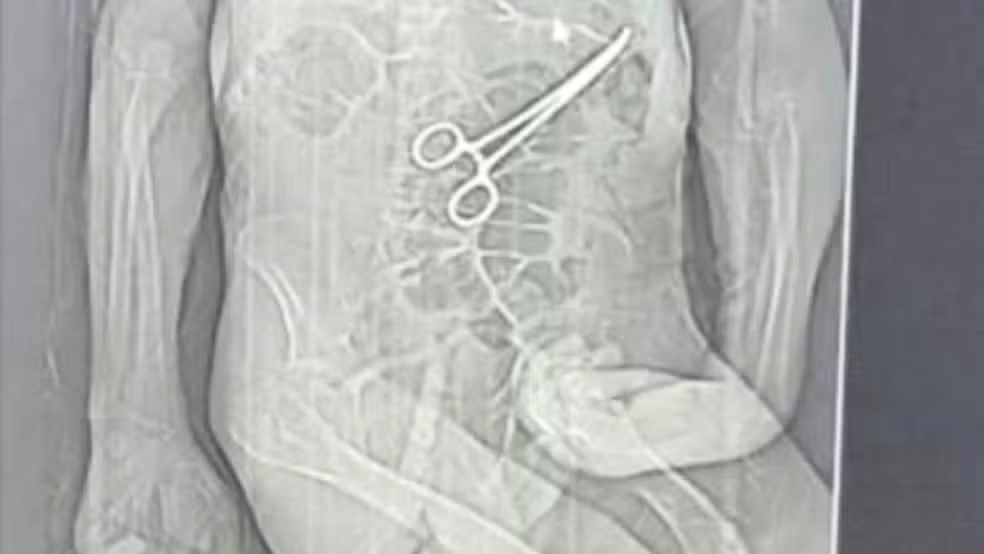

Pinça foi esquecida dentro do corpo Crédito: Rádio Nova FM/Reprodução

Um idoso de 68 anos morreu na véspera do Natal após passar por duas cirurgias no Hospital Municipal de João Pinheiro, no Noroeste de Minas Gerais. A família de Manoel Cardoso de Brito acusa a unidade de saúde de erro médico e afirma que uma pinça cirúrgica foi esquecida dentro do corpo do paciente após o primeiro procedimento. As informações são do g1 MG.

Após a morte, a família teve conhecimento de uma tomografia divulgada por uma rádio local que indicaria a presença de uma pinça cirúrgica dentro do corpo do paciente. Segundo o advogado dos familiares, Iuri Evangelista Furtado, a partir desse exame começaram a ser adotadas medidas legais.